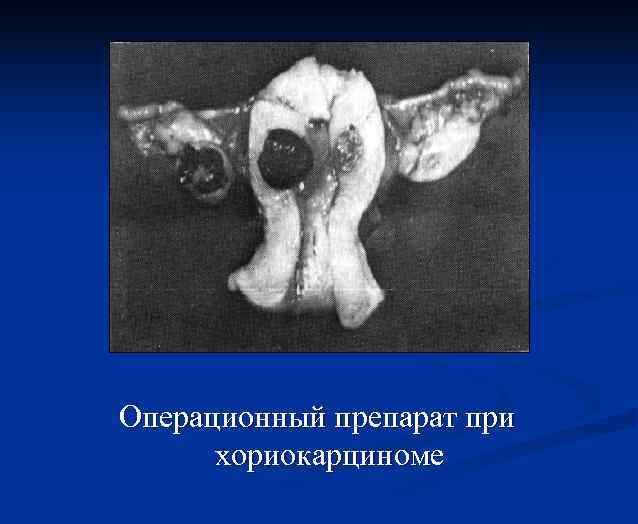

Операционный препарат при хориокарциноме